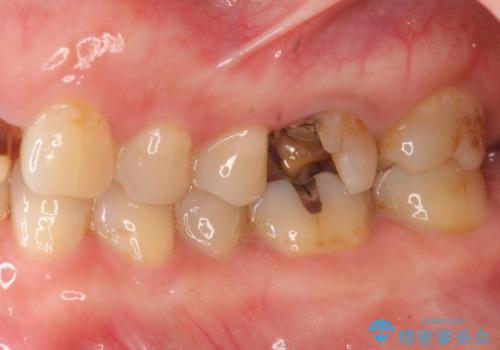

- 銀歯が取れたのち放置してしまいセラミック治療を希望され来院されました。

虫歯の再発も見られたので、丁寧に虫歯を取り除いたのち根管治療を行いジルコニアクラウン・セラミックインレーにより修復処置を行いました。